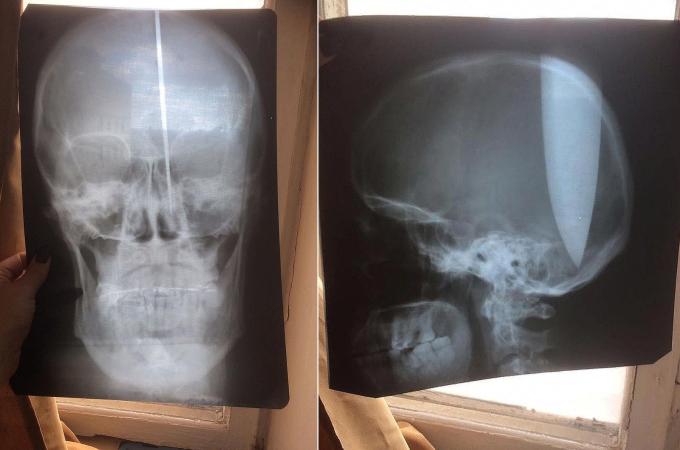

Psychicky narušený muž si do lebky zabodl dlouhý nůž: Nemohl prý dýchat